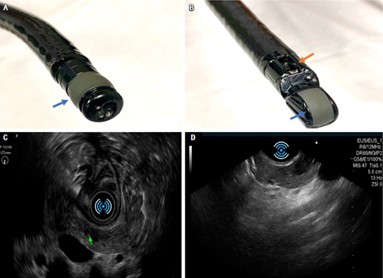

La endosonografía

También conocida como ultrasonografía endoscópica (USE), es una técnica diagnóstica avanzada que combina la endoscopía y la ecografía para obtener imágenes detalladas de las estructuras internas del cuerpo. Este método utiliza un endoscopio flexible equipado con un transductor de ultrasonido en su extremo, lo que permite la visualización de órganos como el páncreas, ganglios linfáticos y tejidos circundantes con alta resolución y precisión.(8)

En el contexto del insulinoma, un tumor neuroendocrino pancreático raro y generalmente pequeño, la endosonografía es una herramienta diagnóstica de gran valor debido a su alta sensibilidad. Estos tumores, que suelen medir menos de 2 cm, pueden ser difíciles de detectar con técnicas convencionales como la tomografía computarizada (TC) o la resonancia magnética (RM). La endosonografía permite localizar lesiones no visibles en otros estudios, alcanzando una sensibilidad de hasta 90% en la detección de insulinomas pequeños o ectópicos.(8)

Los insulinomas aparecen característicamente como lesiones hipoecoicas, homogéneas y bien delimitadas en las imágenes de ultrasonido. Además, esta técnica permite diferenciar estas lesiones de otras patologías pancreáticas, como quistes o tumores sólidos no funcionales. La información proporcionada por la endosonografía es esencial para la evaluación prequirúrgica, ya que facilita la localización precisa del tumor y su relación con estructuras vasculares y conductos pancreáticos, optimizando así el abordaje quirúrgico.(9)

Otra aplicación clave de la endosonografía es la guía para procedimientos intervencionistas, como la punción aspirativa con aguja fina (PAAF). Este procedimiento permite obtener muestras del tumor para un diagnóstico citológico o histopatológico definitivo, lo que resulta crucial en casos de duda diagnóstica.(9)

Aunque presenta ventajas significativas, la endosonografía también tiene limitaciones. Es una técnica operadordependiente, por lo que la experiencia del profesional influye directamente en los resultados. También puede ser menos efectiva en la evaluación de lesiones ubicadas en la cola del páncreas o en áreas alejadas del tracto gastrointestinal. Sin embargo, su bajo riesgo de complicaciones y su capacidad para combinar evaluación diagnóstica y terapéutica la convierten en una herramienta indispensable en el manejo de pacientes con insulinomas.(9)

La endosonografía representa un avance significativo en la detección y manejo de insulinomas, en especial en aquellos casos difíciles de diagnosticar con métodos convencionales. Su aplicación en el diagnóstico, evaluación prequirúrgica y guía de intervenciones mínimamente invasivas subraya su importancia en el abordaje multidisciplinario de esta patología.(6)